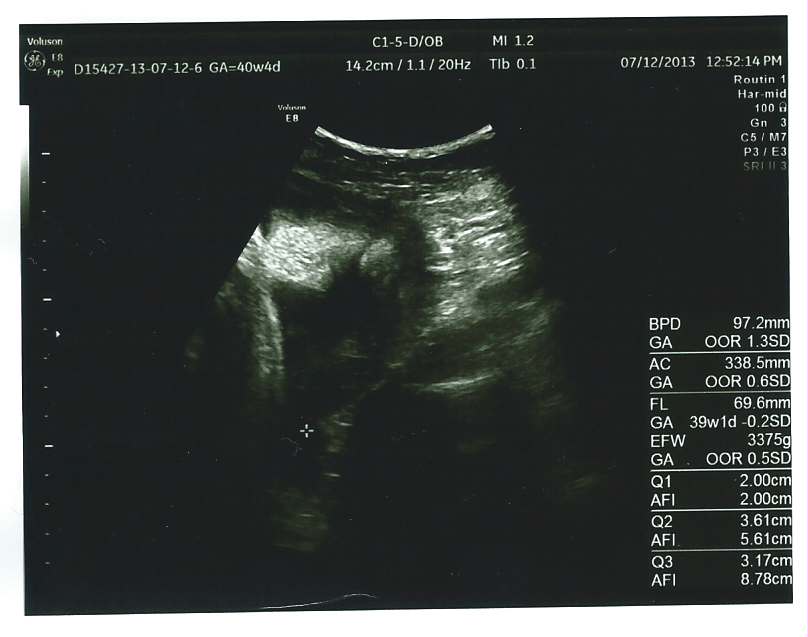

echo